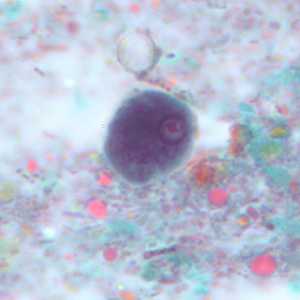

Figure E: Mature cyst of E. coli, stained with trichrome. This figure and Figure F represent the same cyst shown in two different focal planes. Eight nuclei can be seen between the two focal planes. Also, above the cyst in this figure, a trophozoite of Endolimax nana can be seen.

Figure F: Mature cyst of E. coli, stained with trichrome. This figure and Figure E represent the same cyst shown in two different focal planes. Eight nuclei can be seen between the two focal planes.